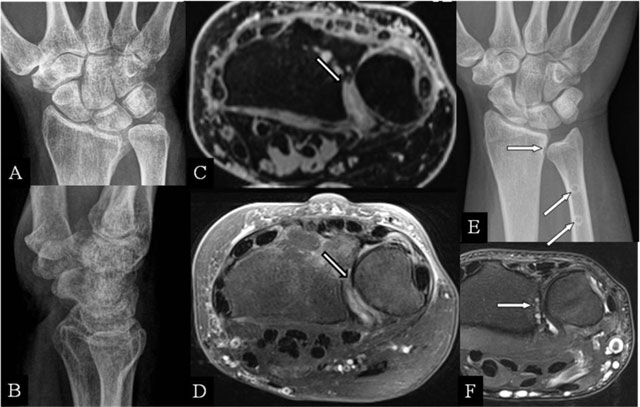

Figure 2

Radioulnar abutment and ulnar impingement. (A, B) PA and lateral plain radiographs; (C) Axial 3D-GRE; (D) SE T2-WI FS; (E) PA plain radiograph; and (F) Axial SE T2-WI FS. (A, B) Sequelae of a Pouteau-Colles fracture of the distal radial epiphysis. (C) Residual step-off at the radial sigmoid notch. (D) Destruction of the cartilage at the dorsal part of the sigmoid notch. (E) Excessive shortening (horizontal arrow) after surgery (oblique arrows). (F) subchondral erosions at the most proximal part of the radial sigmoid notch.

Radioulnar abutment

Distal radioulnar joint (DRUJ) fractures are difficult to evaluate on radiographs, particularly coronal sigmoid notch fractures (Figure 2A and B). Bony incongruity is better evaluated by (cone beam-)CT and a cartilage step-off (Figure 2C and D) by MRI. Pronation and supination may be hampered during the radial movement around the ulna [7]. Even minor deformities may cause severe dysfunction.

Ulnar impingement

A relative ulnar shortening may appear after trauma, causing a DRUJ impingement (Figure 2E and F). Excessive ulnar shortening or resection may cause secondary impingement [8]. The appearance is equal to a congenital short ulna.